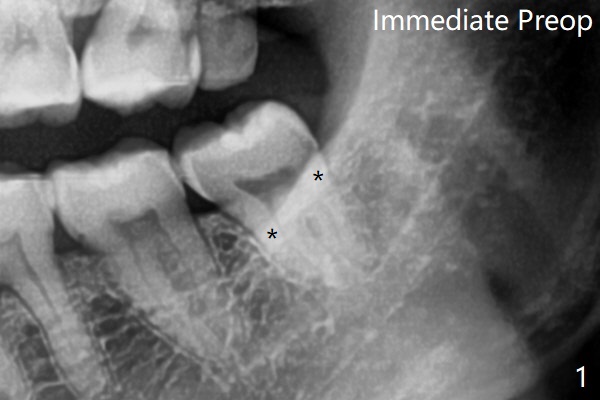

术前外斜脊(图一:*)存在,术后即刻没有消失,放置0.5毫升骨水泥(图二)。